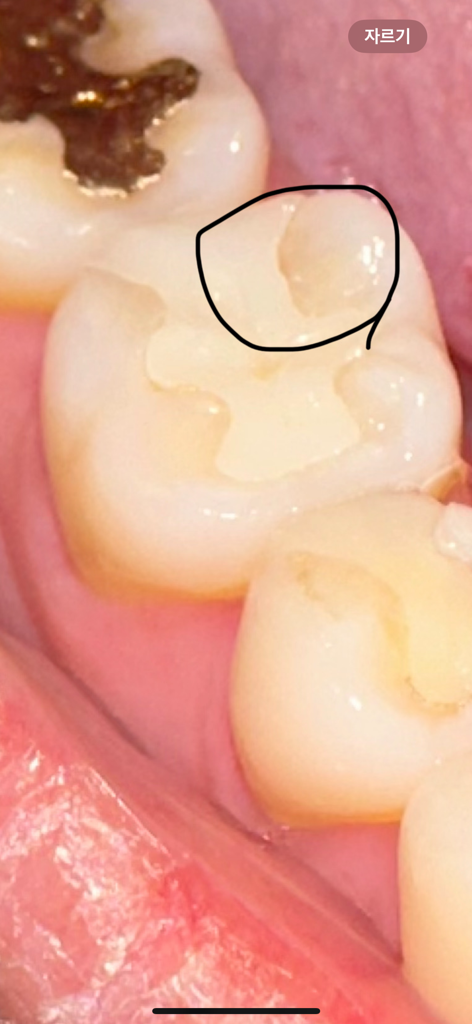

보철물과 치아 사이 틈이 확실히 있는것같은데 틈이 없다고 하시고 전체적으로 다듬어주셨는데 오히려 다른 부분도 더 사이가 벌어진것같은 기분이 들어요.. 저기 밑에 사진 검은부분도 약간 파인것처럼 되었는데 원래 안저렇고 매끄러웠어요 ㅠㅠ 눈으로만 봐도 미세하게 벌어진게 보이는데 왜 다른부분들까지 저렇게 다듬어줘서 파여진 부분도 보이게되고 멀쩡한 부분을 왜 다듬으신건지.. 일반적이라면 교체해야하는게 정상아닌가요 ㅠㅠ 사진도 찍어보자는 말도 안하고.. 이러다 이빨 더 큰 문제되는게 아닐까요..? 위에 사진은 치과 방문 전 이고 밑에 사진이 오늘 다듬은 사진 입니다 전문가분들 도와주세요 ㅠㅠ

• 1번 째 사진